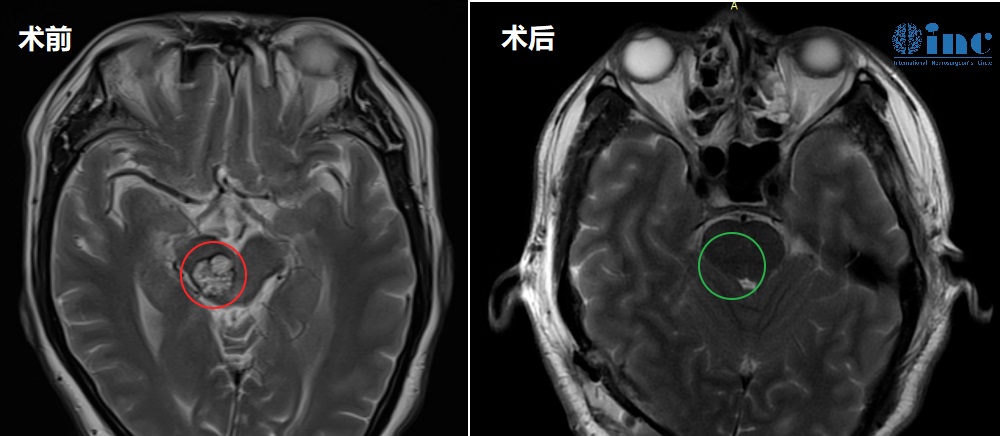

30岁男性-脑干(桥脑)海绵状血管瘤

病史摘要:“从2016年1月份开始,头晕、行走不稳,重影复视。2016年至2018年,我大概有4次出血。18年到现在,出血有3次……”30岁的江先生罹患脑干海绵状血管瘤,血管瘤已经从四脑室鼓出来,一旦再次大量出血,可能带来不可预知的较大风险。手术是的解决办法,但江先生的父母更加担心的是,“我们就是怕手术有后遗症,他还没结婚。从他生病之后,我和他爸爸较担心这个。”

▼脑干海绵状血管瘤术前MRI

治疗过程:2023年11月5日,巴教授为江先生成功手术,脑干海绵状血管瘤得到顺利全切。

术后情况:

术后1天查房,转出ICU,转入普通病房,恢复状况良好。巴教授查房时用中文询问道“今天感觉怎么样?”“Very very good!”,巴教授逐一检查了江先生的吞咽、面部活动、肢体活动等功能,“没问题”,巴教授为江先生的状态点赞。“Thank you very much!”,江先生及家人都无比感谢巴教授。

术后2天查房,江先生的眼睛已经比术前好一些了。术后两周江先生顺利出院。